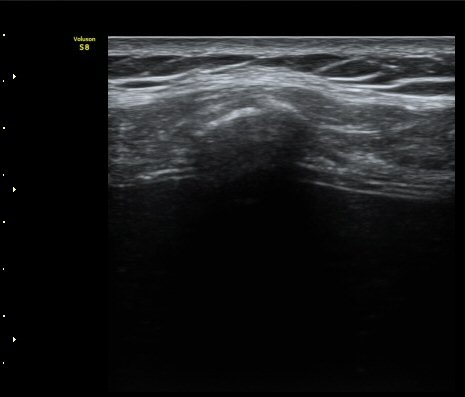

°¥ºñ»À Á¾´Ü¸é°Ë»ç¿¡¼­ °¡°ñ Çü¼ºÀÌ °üÂûµÊ(formation of callus) »çÁø 3

°¥ºñ»À Ⱦ´Ü¸é°Ë»ç¿¡¼­ °¡°ñ Çü¼ºÀÌ °üÂûµÊ(formation of callus)   »çÁø 4

°ñ À¯ÇÕÀÌ È®ÀεÊ.